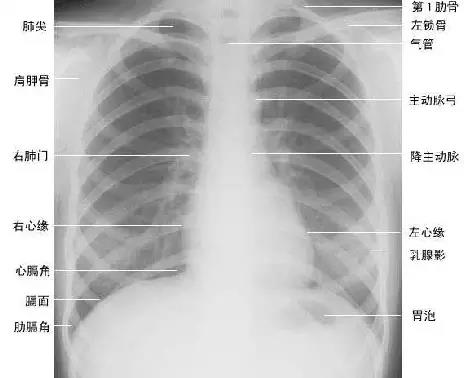

下面为大家依次介绍胸部正常X线解剖

1.肺叶段X线解剖

2.肺纹理

肺纹理为自肺门向肺野呈放射状分布的树枝状阴影,它主要是肺动脉的投影,肺静脉、支气管和淋巴管也参与形成。肺纹理由肺门向外围延伸,逐渐变细,至肺野外带渐细小而稀少,距侧胸壁内缘约1cm范围内的肺野基本无肺纹理可见(图下图)。

3.肺野、肺带的划分

纵隔两旁含气的肺在胸片上所显示的透明区域称肺野,其透明度随呼吸而改变,深吸气时肺内含气量增多,透明度增高,呼气时则相反。

为便于指明病变的部位,通常人为地将一侧肺野纵向分为三等分,即内、中、外带。又分别在两侧第2、4肋骨前端下缘划一水平线,将肺野横向分为上、中、下三个肺野。(如上图)。